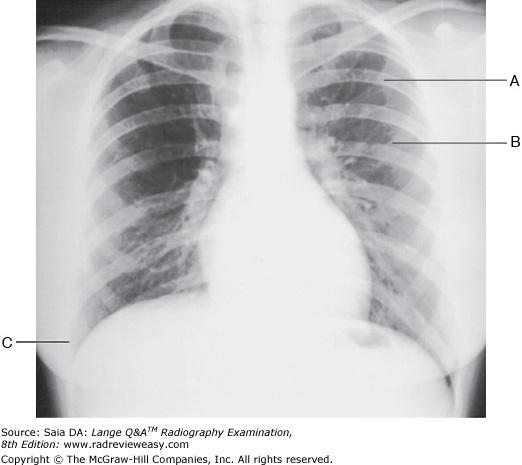

Which of the following statements is (are) true regarding the radiograph shown in Figure 6–16?

B 2 only

-The patient is well positioned; the spinous processes and sternum are seen clearly without superimposition. Adequate penetration and long-scale contrast are present without excessive receptor exposure. The patient had been shielded properly for the PA projection, but the shield was not moved to the correct location prior to the lateral exposure.